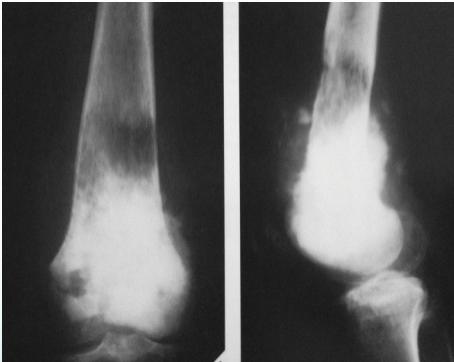

Radiological Features

- X-ray:

- Radiolucency and sclerosis

- Poorly defined margins

- Extends into soft tissue

- Periosteal reaction:

- Sunburst (sun-ray) appearance

- Codman’s triangle

Source: Orthopedic Radiology. A Greenspan. Lippincott-Raven